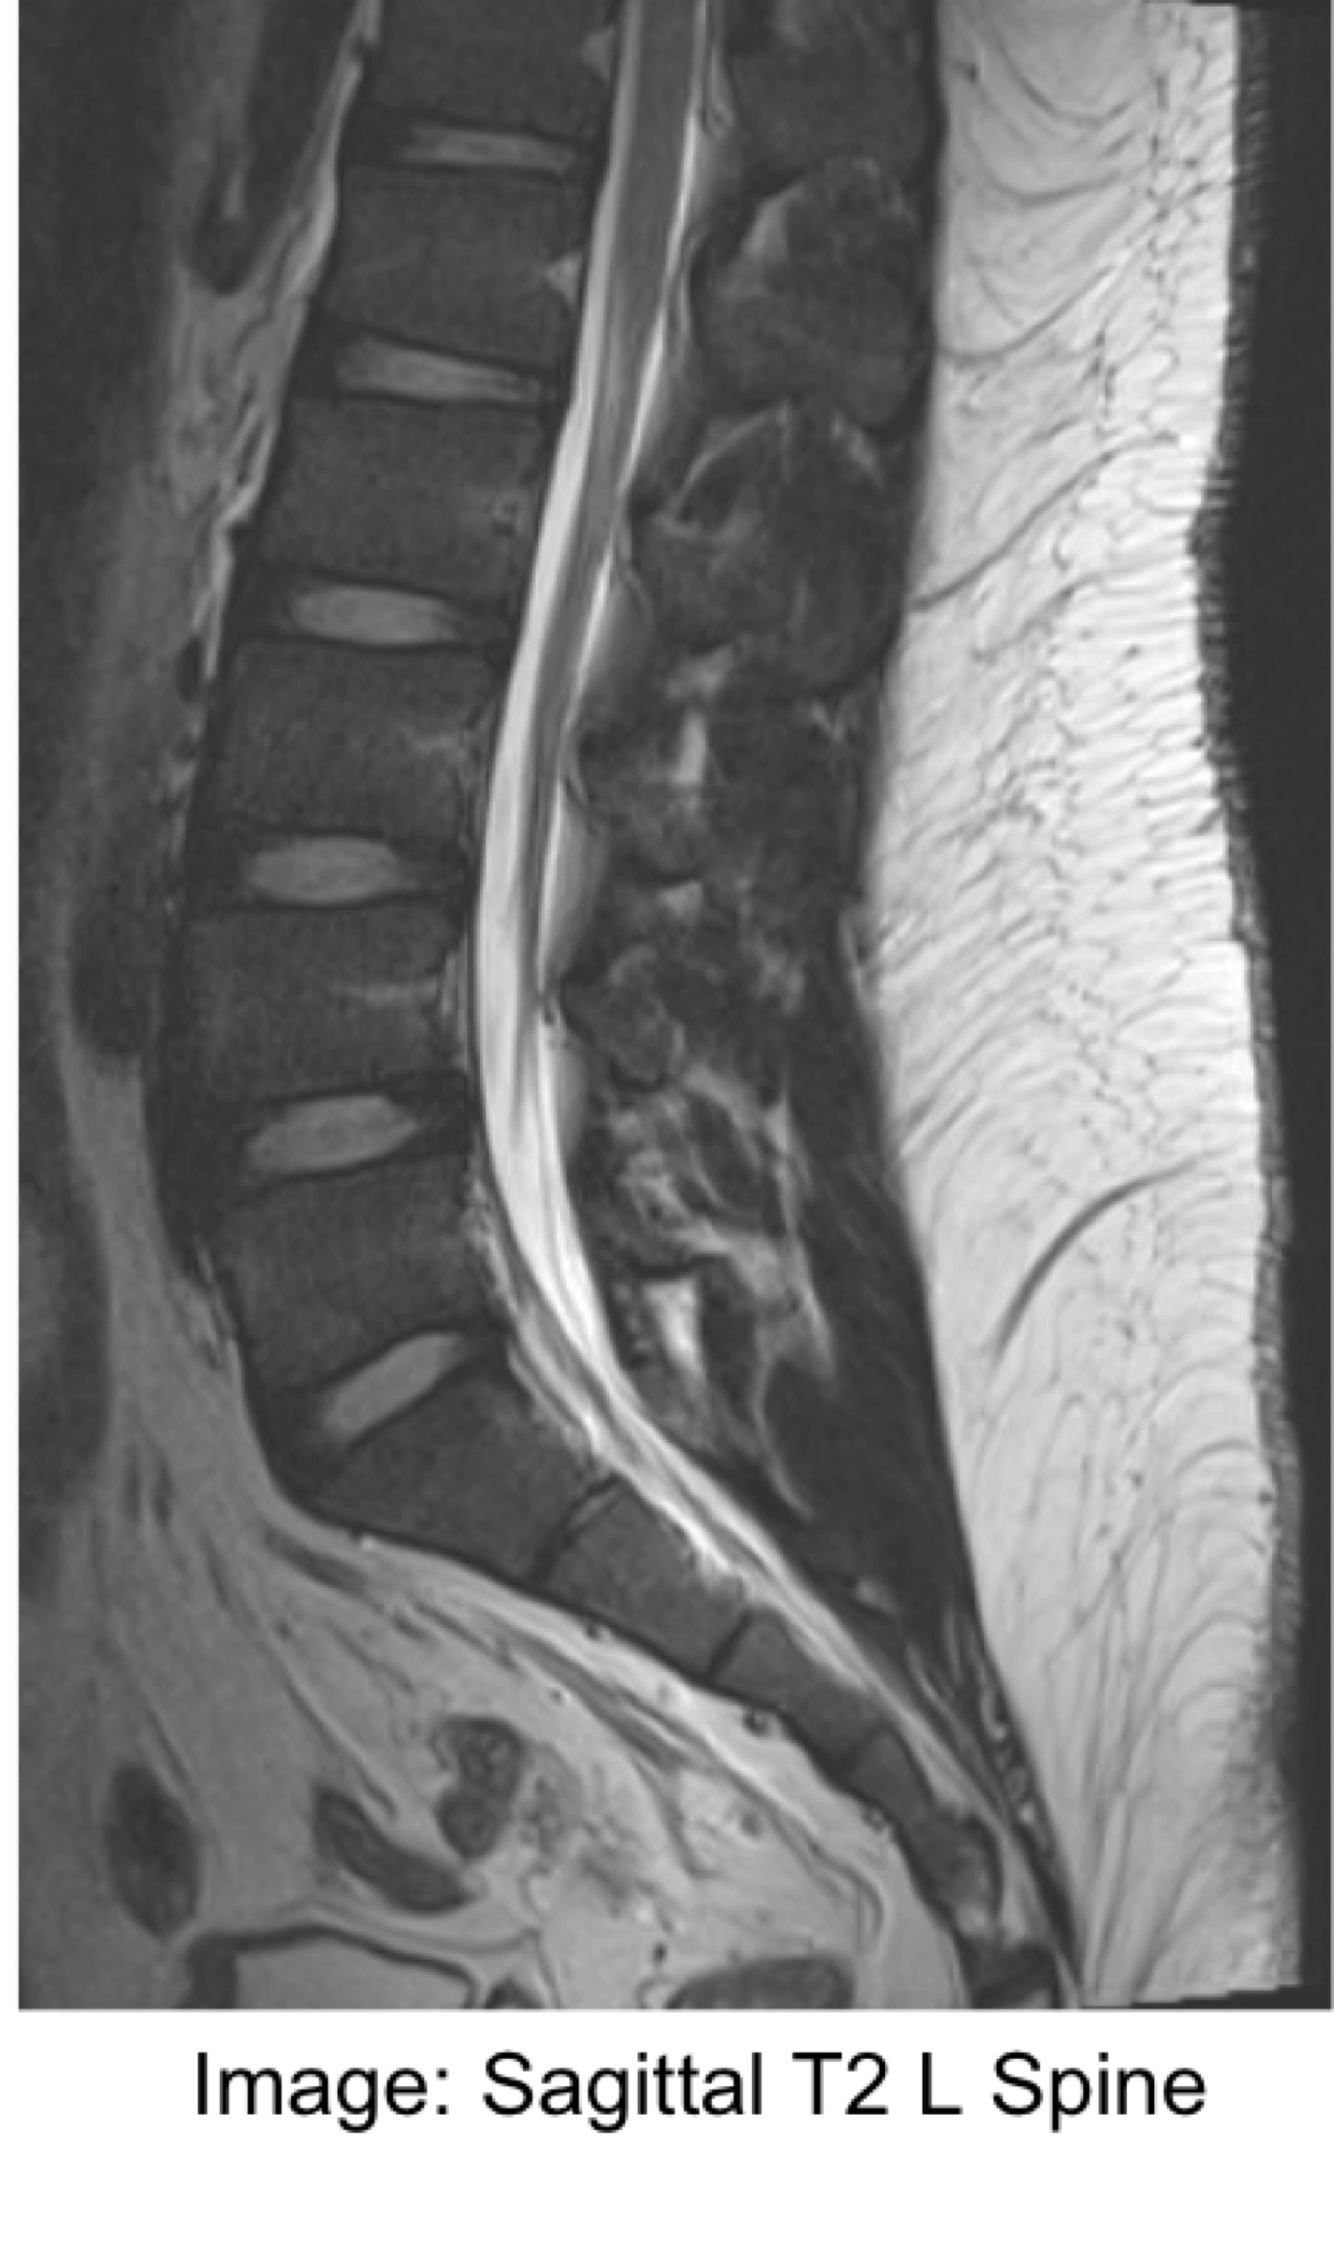

Image contrast:

The … can be separated into individual … of different tissues

Areas of high signal (… on image) are tissues that have a large component of … magnetism at the time of TE

Tissues with a low signal component of … magnetisation at the time of TE will appear …

The NMV can be separated into individual VECTORS of different tissues

Areas of high signal (WHITE on image) are tissues that have a large component of TRANSVERSE magnetism at the time of TE

Tissues with a low signal component of TRANSVERSE magnetisation at the time of TE will appear DARK